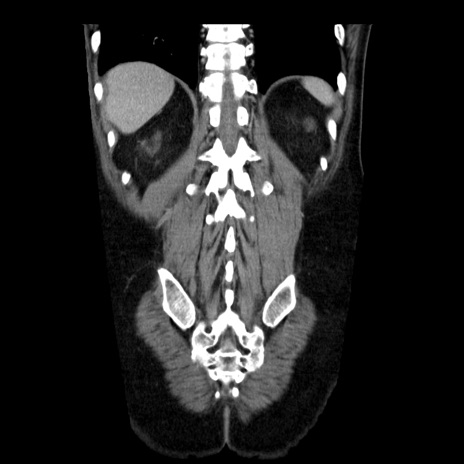

症例29(冠状断像)

【症例】40歳代男性

【現病歴】2日前から胃痛あり。徐々に周期的な激痛に変化した。本日になっても激痛があるため受診。

【身体所見】意識清明、BT 38-39℃台あり、腹部:膨満、やや硬、右下腹部に圧痛あり。

【データ】WBC 8500、CRP 23.26